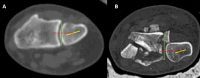

Wrist fractures and dislocations are frequently encountered in the emergency department and can cause significant long-term disability. Imaging plays a crucial role in the evaluation of wrist injuries, with conventional radiography being the first imaging investigation. Cross-sectional imaging is playing an increasingly important role in management of wrist injuries. Computed tomography with 3D and multiplanar reformatting capabilities is in particular useful for detailed evaluation of bony injuries and can provide vital information to orthopaedic surgeons for adequate surgical planning. In this article, we provide a brief review of the normal wrist anatomy, imaging appearance, and various patterns of fractures and dislocations commonly encountered in the emergency department.